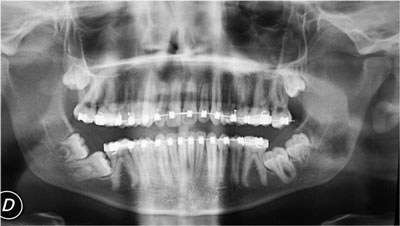

- Tratamientos de las inclusiones dentarias (extracción de cordales o muelas del juicio, extracción de caninos incluidos, extracción de dientes supernumerarios, etc.).

- Exéresis de quistes y tumores de los maxilares.

- Cirugía periapical (legrado, apicectomía y obturación retrograda).

- Cirugía implantológica (colocación de implantes en los maxilares).